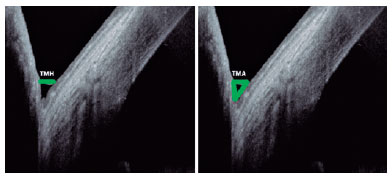

The optical coherence tomography (OCT) measurements were conducted using the Spectralis OCT imaging platform (Heidelberg Engineering GmbH, Heidelberg, Germany). Both the lower tear meniscus height (TMH) and the tear meniscus area (TMA) were measured using the Spectralis OCT, with the lens of the anterior segment, in addition to an image-capturing software in the following mode: sclera, high-speed, single-vertical scan. Using the same device, we took scans in the same region, exactly below the corneal vertex, and centered on the inferior cornea and the lower eyelid(17). Furthermore, we used a built-in caliper to measure the TMH in micrometers and the area in square millimeters (Figure 1).

08-fig01.jpg)